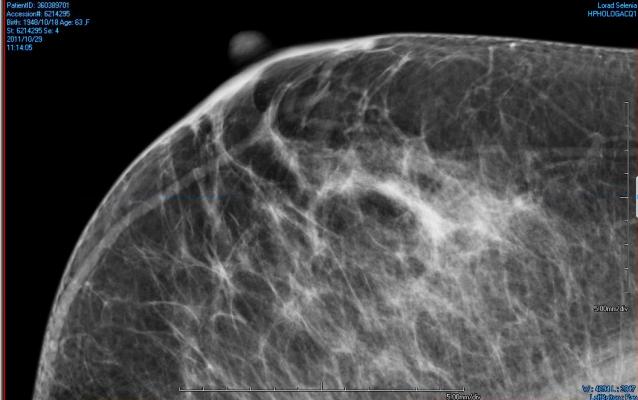

Interpreting screening mammograms is a difficult and repetitive visual search task, for which characteristics of cancer are disguised among background breast parenchyma (tissue), resulting in false-positive recalls and missed cancers. In similar visual search tasks, a vigilance decrement (decreasing detection rates with time on task) has been observed in a large number of psychological laboratory experiments, including assembly line inspection tasks and airport baggage screening. In the United Kingdom (U.K.), two film readers independently evaluate each mammogram for signs of cancer.

Sian Taylor-Phillips, Ph.D., of the University of Warwick, Coventry, U.K., and colleagues investigated whether a vigilance decrement to detect cancer in breast screening practice exists and whether changing the order in which two experts examined a batch of mammograms could increase the cancer detection rate, through readers' experiencing peak vigilance at differing points within the reading batch.